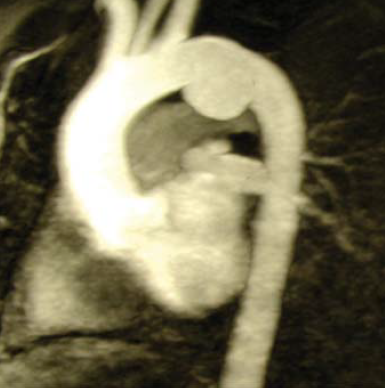

1. 26 éves ffi autóbalesetben utasként szenvedett el mellkasi zúzódást, bordarepedést és tüdő contusiót. A kiszélesedett mediastinum és kis mennyiségű mellkasi folyadékgyülem vetette fel isthmicus tompa aortasérülés lehetőségét, amit DSA vizsgálattal igazoltunk. Hypotenziv kezelés mellett keringése stabil, a mediastinum kiszélesedése és haematologiai statusa nem változott. 3 héttel a sérülést követően bal oldali thoracotomia útján aorto-aorticus Dacron grafttal, mesterséges keringés alkalmazása nélkül, interpositiot végeztünk (1.,2.,3. ábra).

2. ábra.

Az 1. ábrán bemutatott eset intraoperatív képe.

3. ábra.

A műtéti megoldás a sérült szakasz resectioja és aorto-aorticus graft interpositio volt. A graftot részben pleura lemezzel fedtük a tüdő letapadás meggátlása céljából.